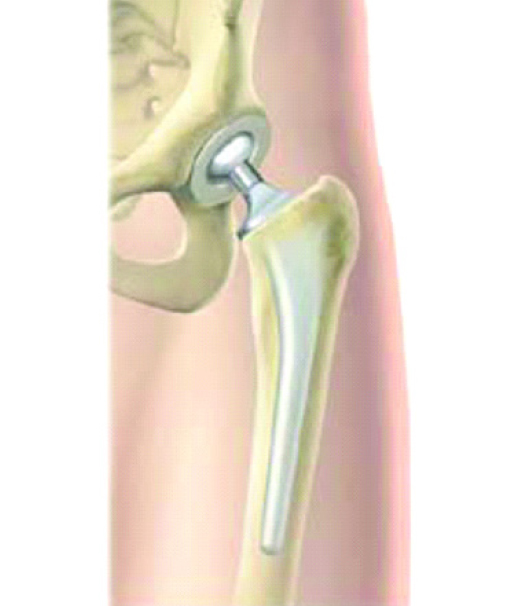

This is a partial hip replacement

If the fracture is in the neck of the femur, the blood supply to the head of the femur will be compromised, and a partial or total hip replacement will be necessary.